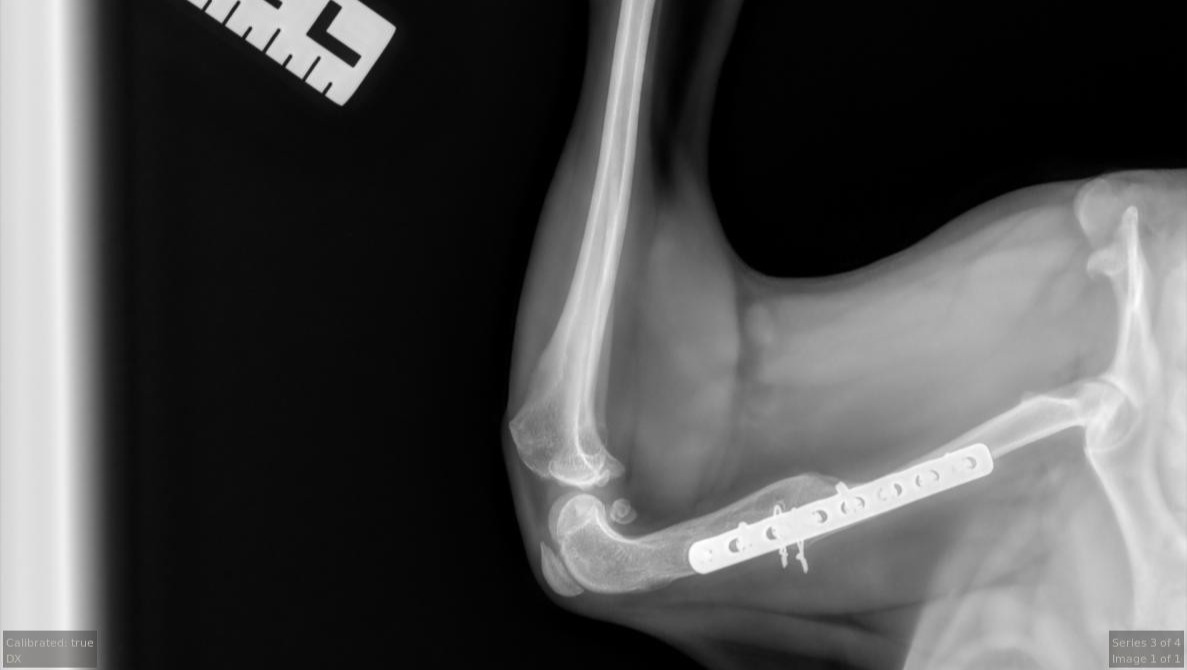

One year ago, we shared the story of a little dog in Puerto Rico who had nearly given up hope. Juanita was found lying on the side of the road in the blistering heat, unable to move after being hit by a car. She had multiple fractures in her pelvis and femur, and her tail was so badly damaged it required amputation. Someone had left a solo cup with water nearby, but she was too broken and weak to reach it. Cars drove past her for days, and when Ruby finally arrived to rescue her, she could barely lift her head. The look in her eyes said it all—she had been waiting for someone to finally care.

Thanks to the generosity of so many kind people, we were able to get Juanita into emergency surgery and start her on the long path toward recovery. Against all odds, she survived. Our on the ground director in Puerto Rico, Ruby, spent many long days and nights caring for Juanita through those first few scary months. Once she was stable enough, she made the journey from Puerto Rico to Colorado, where our rescue founder, Ela, welcomed her into her home.

But Juanita’s story isn’t over yet. Earlier this year, Juanita needed another surgery on her leg to support her recovery and give her the best chance at a healthy future. She has been incredibly brave through every procedure, every setback, and every step forward. While she continues to improve, her medical costs have added up significantly once again. Between her additional surgery, ongoing care, training, and recovery, the expenses have exceeded what our small rescue can cover on our own.